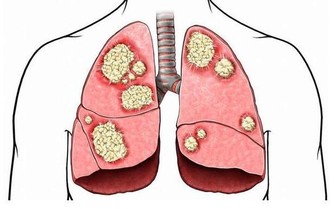

趁熱吃,會致癌?

趁熱吃,確有致癌風險!

世界衛生組織(WHO)下屬的國際癌症研究機構(IARC)早已發布過警告:“ 進食65攝氏度以上熱飲有致癌風險 ”。

偶爾的燙傷還可以自我修復,但經常吃熱燙食物的人,食管在反复損傷和修復的過程中,不正常的“異型性”細胞會越來越多。長此以往,就算不得癌,口腔潰瘍、食管潰瘍等問題也會不期而至。

判斷是否超過65℃的方法很簡單,感覺食物不燙口就可以了。